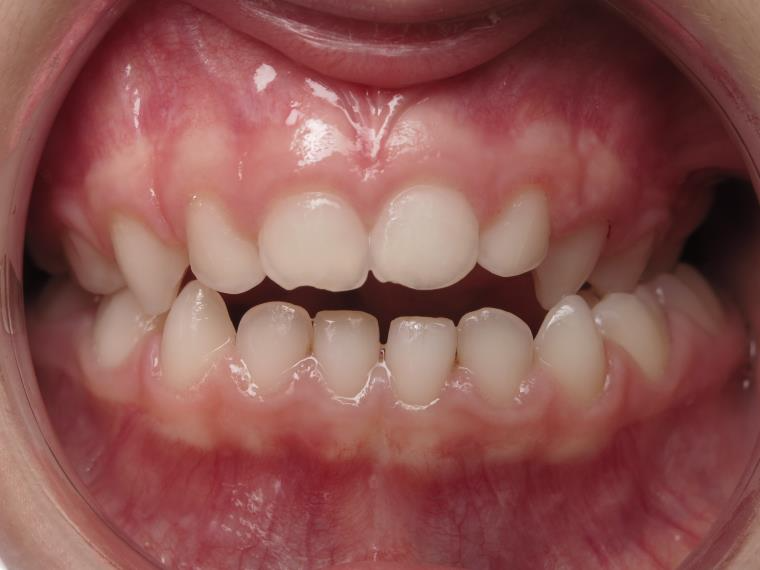

14 béance inversé gauche 5 ans

inversion postérieur coté droit et espace entre l'arcade du haut et du bas (béance)

appareillage mobile pendant 5 mois